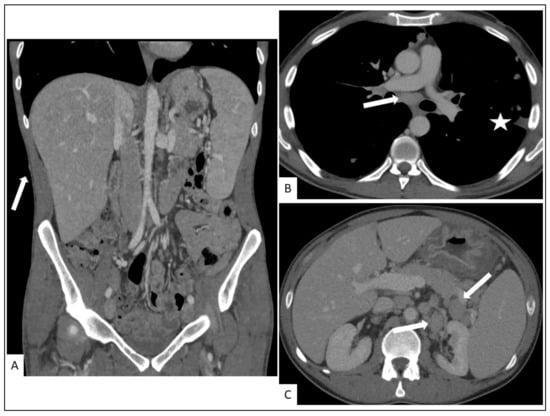

5.2. Hepato-Splenic KS

5.3. Other Visceral Involvement